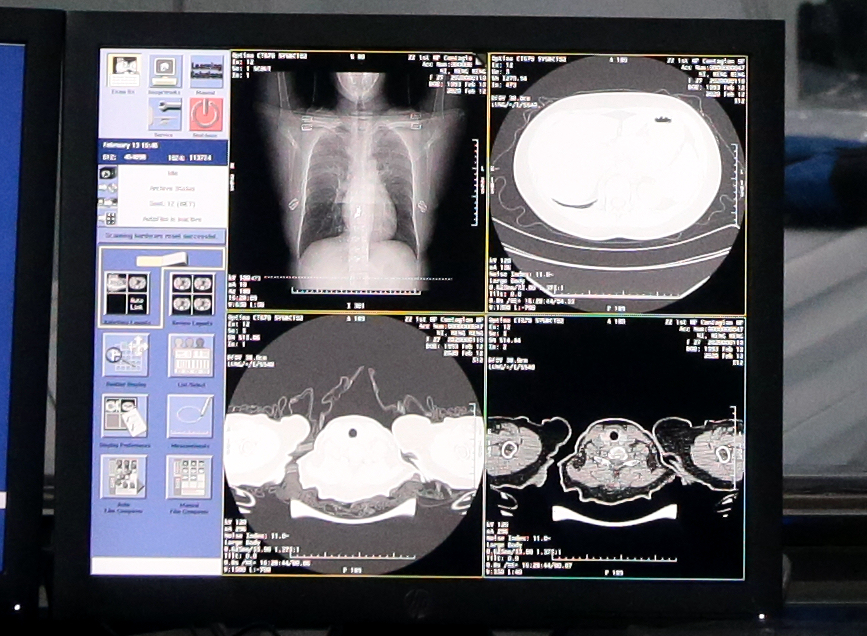

新冠肺炎患者的CT胸片的影像特征表现为单肺或双肺多发、斑片状或节段性磨玻璃密度影等细微变化。一位新冠肺炎病人的CT影像大概在300张左右,这给医生临床诊断带来巨大压力,医生对一个病例的CT影像肉眼分析耗时大约为5-15分钟。

达摩院医疗AI团队基于当前最新的诊疗方案、钟南山等多个权威团队发表的关于新冠肺炎患者临床特征的论文,与浙大一附院、万里云、长远佳和古珀医院等多家机构合作,率先突破了训练数据不足的局限,基于5000多个病例的CT影像样本数据,学习训练样本的病灶纹理,研发了全新的AI算法模型。